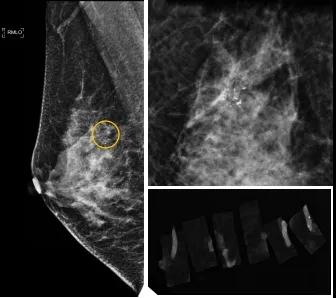

小到1—2mm的鈣化也能活檢!西安國際醫(yī)學(xué)中心醫(yī)院采用精準(zhǔn)技術(shù)讓乳腺早癌無處可逃

46歲的某女士在西安國際醫(yī)學(xué)中心醫(yī)院體檢時(shí),行乳腺X線攝影(俗稱鉬靶)發(fā)現(xiàn)右乳可疑簇狀鈣化,分布范圍不到1厘米,臨床觸不到,超聲很難發(fā)現(xiàn),但是這種鈣化風(fēng)險(xiǎn)比較高,依據(jù)國際BI-RADS指南需要明確病理!

西安國際醫(yī)學(xué)中心醫(yī)院影像診療中心陳寶瑩副主任帶領(lǐng)的團(tuán)隊(duì),采用全數(shù)字化乳腺X線三維立體定位系統(tǒng)可實(shí)施。這個(gè)團(tuán)隊(duì)的成員大部分來自知名三甲醫(yī)院,有著十余年影像引導(dǎo)下乳腺介入診療的經(jīng)驗(yàn),X線引導(dǎo)穿刺定位和活檢例數(shù)居西北前列。為減少患者創(chuàng)傷,在詳細(xì)判讀了患者資料,并與患者及甲乳外科劉曉敏主任充分溝通的基礎(chǔ)上,團(tuán)隊(duì)確定采用全數(shù)字化乳腺X線三維立體定位系統(tǒng)下實(shí)施粗針活檢。

當(dāng)天,乳腺X線三維立體定位系統(tǒng)清晰顯示出了所有鈣化。為了獲取充足的組織量,保證病理診斷的準(zhǔn)確性,團(tuán)隊(duì)選用14G穿刺針并多點(diǎn)、多角度取材,組織取出后,又立即在高清標(biāo)本攝影系統(tǒng)中進(jìn)行投照,從而確定了取出組織中具有足夠的可疑鈣化。整個(gè)過程患者無任何不適,活檢結(jié)束后即回家觀察。

后期病理回報(bào)活檢組織條中均查見導(dǎo)管原位癌。該女士及家屬對(duì)西安國際醫(yī)學(xué)中心醫(yī)院早期發(fā)現(xiàn)并精準(zhǔn)確診病變的技術(shù)給予了高度的贊揚(yáng)。

乳腺導(dǎo)管原位癌屬于早期的腫瘤性導(dǎo)管內(nèi)病變,有發(fā)展為浸潤性癌的傾向,需要早發(fā)現(xiàn)早治療,其預(yù)后明顯優(yōu)于浸潤性癌。2020年癌癥雜志的文章指出,近90%的導(dǎo)管原位癌僅表現(xiàn)為不可觸及的可疑鈣化,乳腺X線檢查是發(fā)現(xiàn)微小鈣化最敏感的方式,因此70–90%的導(dǎo)管原位癌是通過乳腺X線篩查發(fā)現(xiàn)。多年來國內(nèi)外指南,如美國國家綜合癌癥網(wǎng)絡(luò)(NCCN)指南及中國抗癌協(xié)會(huì)乳腺癌診治指南均建議40歲以上女性每年通過雙乳X線檢查(鉬靶)進(jìn)行乳腺癌篩查,高危人群建議提前進(jìn)行篩查(小于40歲)。由于雙乳X線篩查的推廣,歐美等國家導(dǎo)管原位癌的檢出率極大提高,明顯降低了乳腺癌的死亡率。在我國規(guī)范進(jìn)行乳腺X線篩查的人群比例比較低,很多人發(fā)現(xiàn)腫瘤時(shí)已經(jīng)為浸潤性癌,因此提醒大家高度重視規(guī)范的雙乳X線篩查。通過乳腺X線篩查發(fā)現(xiàn)的可疑鈣化需要在X線引導(dǎo)下精準(zhǔn)定位,進(jìn)行粗針穿刺或真空輔助旋切活檢,以獲得準(zhǔn)確的病理學(xué)結(jié)果,給予及時(shí)有效的治療。